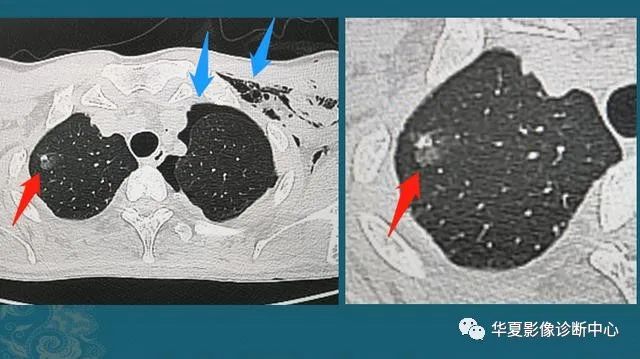

下图是一位30岁年轻人,车祸外伤,撞断3根肋骨,并造成肺挫伤、出血(创伤性湿肺):

红箭头这里的一小片肺组织被车祸撞击暴力撕裂,小血管破裂出血,形成不均匀的高密度影;蓝箭头是气胸和皮下气肿(肺破了,肺里空气溢出到胸腔和肌肉间隙内)。

这种程度的创伤没有生命危险,保守治疗1周出院了,后来小伙子复查CT,肺里留下了一个3 mm的光滑小结节:

图2

这是个良性实性小结节,是血肿吸收不彻底形成的,不要紧,不需要定期复查。